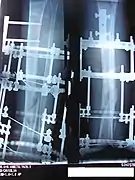

The photographs and radiographs illustrate the application and emplacement of an external fixator, an Ilizarov apparatus, to repair the open fracture of the lower left leg of a man. The photographs were taken four weeks after the patient fractured the shinbone (tibia) and the calfbone (fibula) of his left leg, and two weeks after the surgical emplacement of the Ilizarov apparatus to immobilise the leg and isolate the wound and fracture site to facilitate healing.

X-ray of the fracture site and the emplaced apparatus, two months post-fracture; perspective 2-4.

X-ray of the callus forming at the fracture site, three months post-fracture; perspective 3-4.

X-ray of the callus forming around the fracture site, three months post-fracture; perspective 4-4.

X-ray perspectives of the callus-formation progress and healing of the fractured tibia and fibula bones, four months post-fracture.